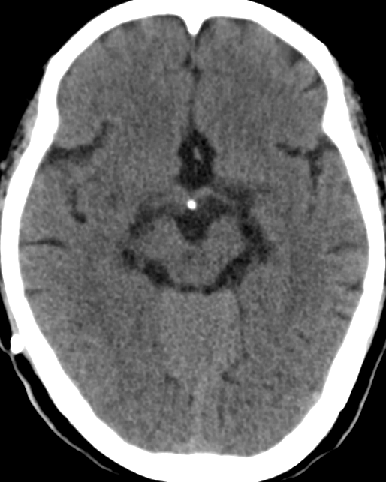

2014-2-10 CT

仍诉头痛,调压150——170

2014-3-17 CT

头痛无明显好转,调压170——190

2014-10-17 CT

仍时有前额部疼痛,程度轻,调压190—200